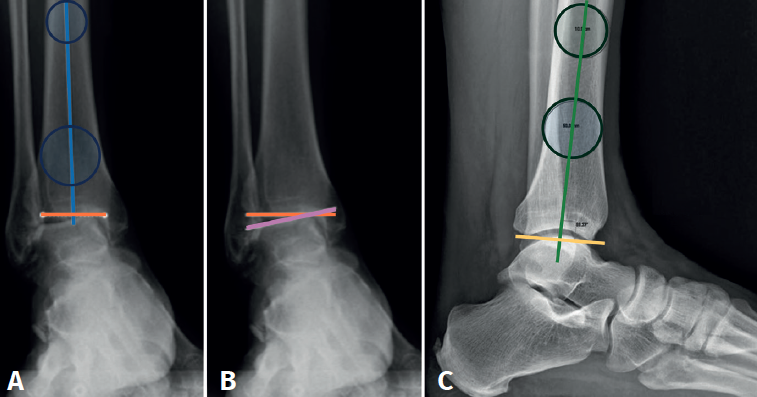

La alineación supramaleolar del tobillo debe evaluarse en los planos coronal y sagital, midiendo el ángulo tibial distal anterior y el ángulo tibial distal lateral, respectivamente.

En la proyección anterior de tobillo evaluaremos el talar tilt o ángulo de inclinación del astrágalo, aumentado en las lesiones incongruentes intraarticulares (Figura 1).

reaca.32284.fs2505013-figura1.png

Figura 1. A: ángulo tibial distal anterior, entre el eje anatómico de la tibia en el plano posteroanterior y la línea de la superficie articular distal de la tibia; B: ángulo de inclinación astragalina (talar tilt), formado entre la línea de la superficie articular tibial y la línea de la superficie articular astragalina. Evalúa la congruencia articular; C: ángulo tibial distal lateral, entre el eje anatómico lateral de la tibia y la línea de la superficie articular distal lateral de la tibia.